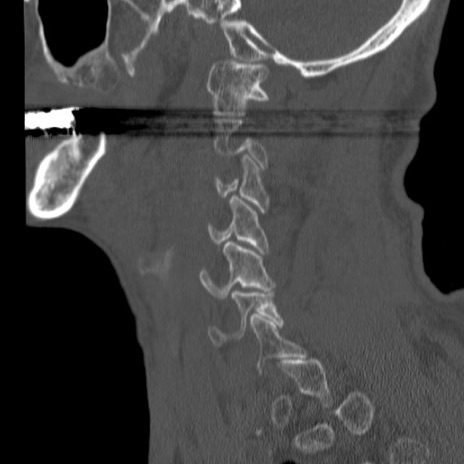

症例46 頚椎CT(矢状断像)

【症例】80歳代男性

【主訴】両側頚部〜上肢のしびれ

【現病歴】昨日、自宅内で転倒、その後より上記症状あり。意識障害なし。

【身体所見】両側上肢のallodynia(熱痛覚過敏)あり。MMTおよびDTRは正確な所見取れず。両上肢の挙上はなんとか可能。

異常所見と診断は?